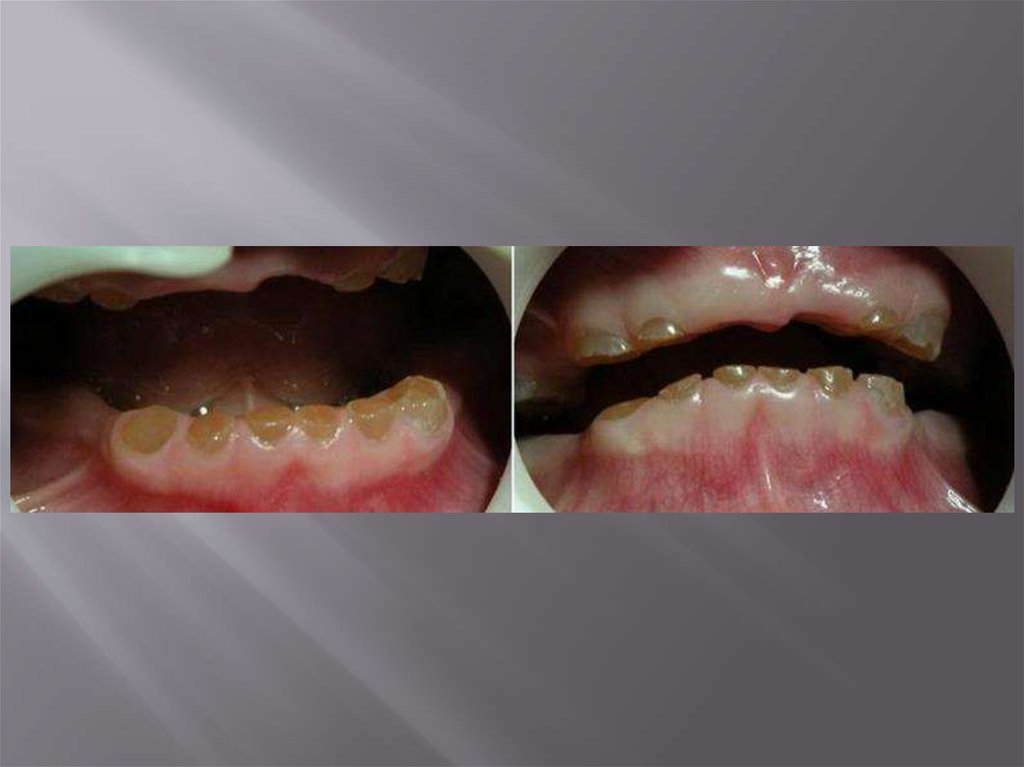

При несовершенном дентиногенезе II

типа зубы имеют желто-коричневый цвет,

лишены эмали, быстро стираются; дентин

прозрачный, сквоз него просвечивает

пульпа. Зубы легко крошатся, корни

короткие и тонкие. ЭОД пульпы обычно

понижена, чувствительность к химическим

и физическим раздражителям тоже. В

дентине больше воды чем в норме, а

неорганических солей существенно

меньше.